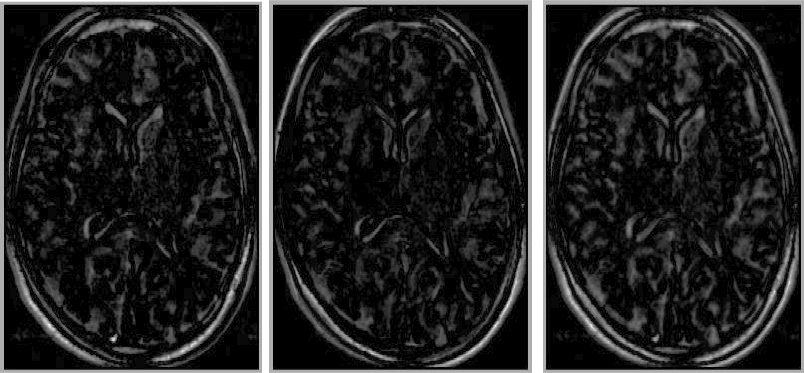

Figure: Examples of the shuffle difference image: from first to second (left), from second to first (centre), and the symmetrical shuffle difference image (right)

Image shuffle_images-revised